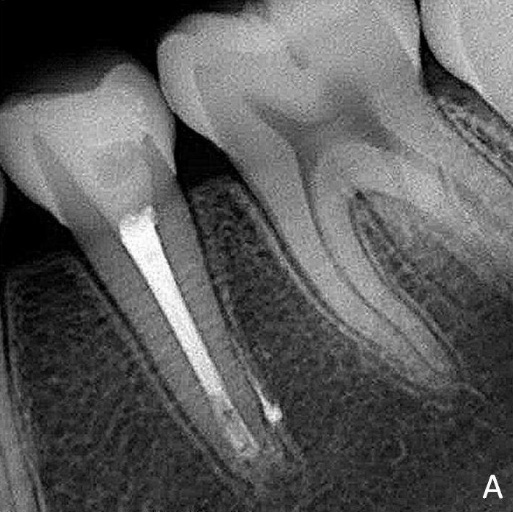

A 12-year-old female patient came to the Dental Hospital of the Federal University of Uberlândia (HO/UFU) reporting a spontaneous, diffuse, intermittent, long-lasting pain exacerbated by chewing plus cold and hot stimuli. Tooth 35 had a coronary access performed in a private dental practice six months earlier. Radiographically, unsatisfactory coronary access, thickening of the periodontal ligament, a diffuse periapical lesion and the presence of an open apex were observed (Figure 1A).

Figure 1A. Radiographic aspects after removal of the provisional restoration.